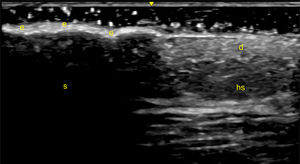

Psoriatic plaques exhibit a range of ultrasound characteristics, most notably a significant thickening of both the epidermis and dermis, often accompanied by increased vascularity in the dermis, as revealed by PD. In certain cases, the degree of epidermal thickening is so substantial that it creates an acoustic shadow impairing the visualization of deeper structures (Fig. 4) [20].

Fig. 4.Psoriatic plaque. Sonographic image obtained using Logiq e US system with an 8–18i MHz linear transducer. Comparative image of the edge of a psoriatic plaque, distinguishing healthy skin (hs) from the plaque itself. Note the thickening of the epidermis (e), which generates an acoustic shadow (s), hindering the visualization of deeper structures. d=dermis.

Though typical of psoriatic skin, these sonographic features may overlap with other dermatological conditions, such as contact dermatitis, atopic eczema, or acanthomas [127]. It is also important to account for variations in skin thickness due to factors like gender, sun exposure, and body region, requiring comparisons between lesional and non-lesional skin in the same anatomical area [126]. Ultrasound allows monitoring of treatment response, demonstrated by a reduction in epidermal and dermal thickness and the resolution of the superficial hypoechoic band [129,130].